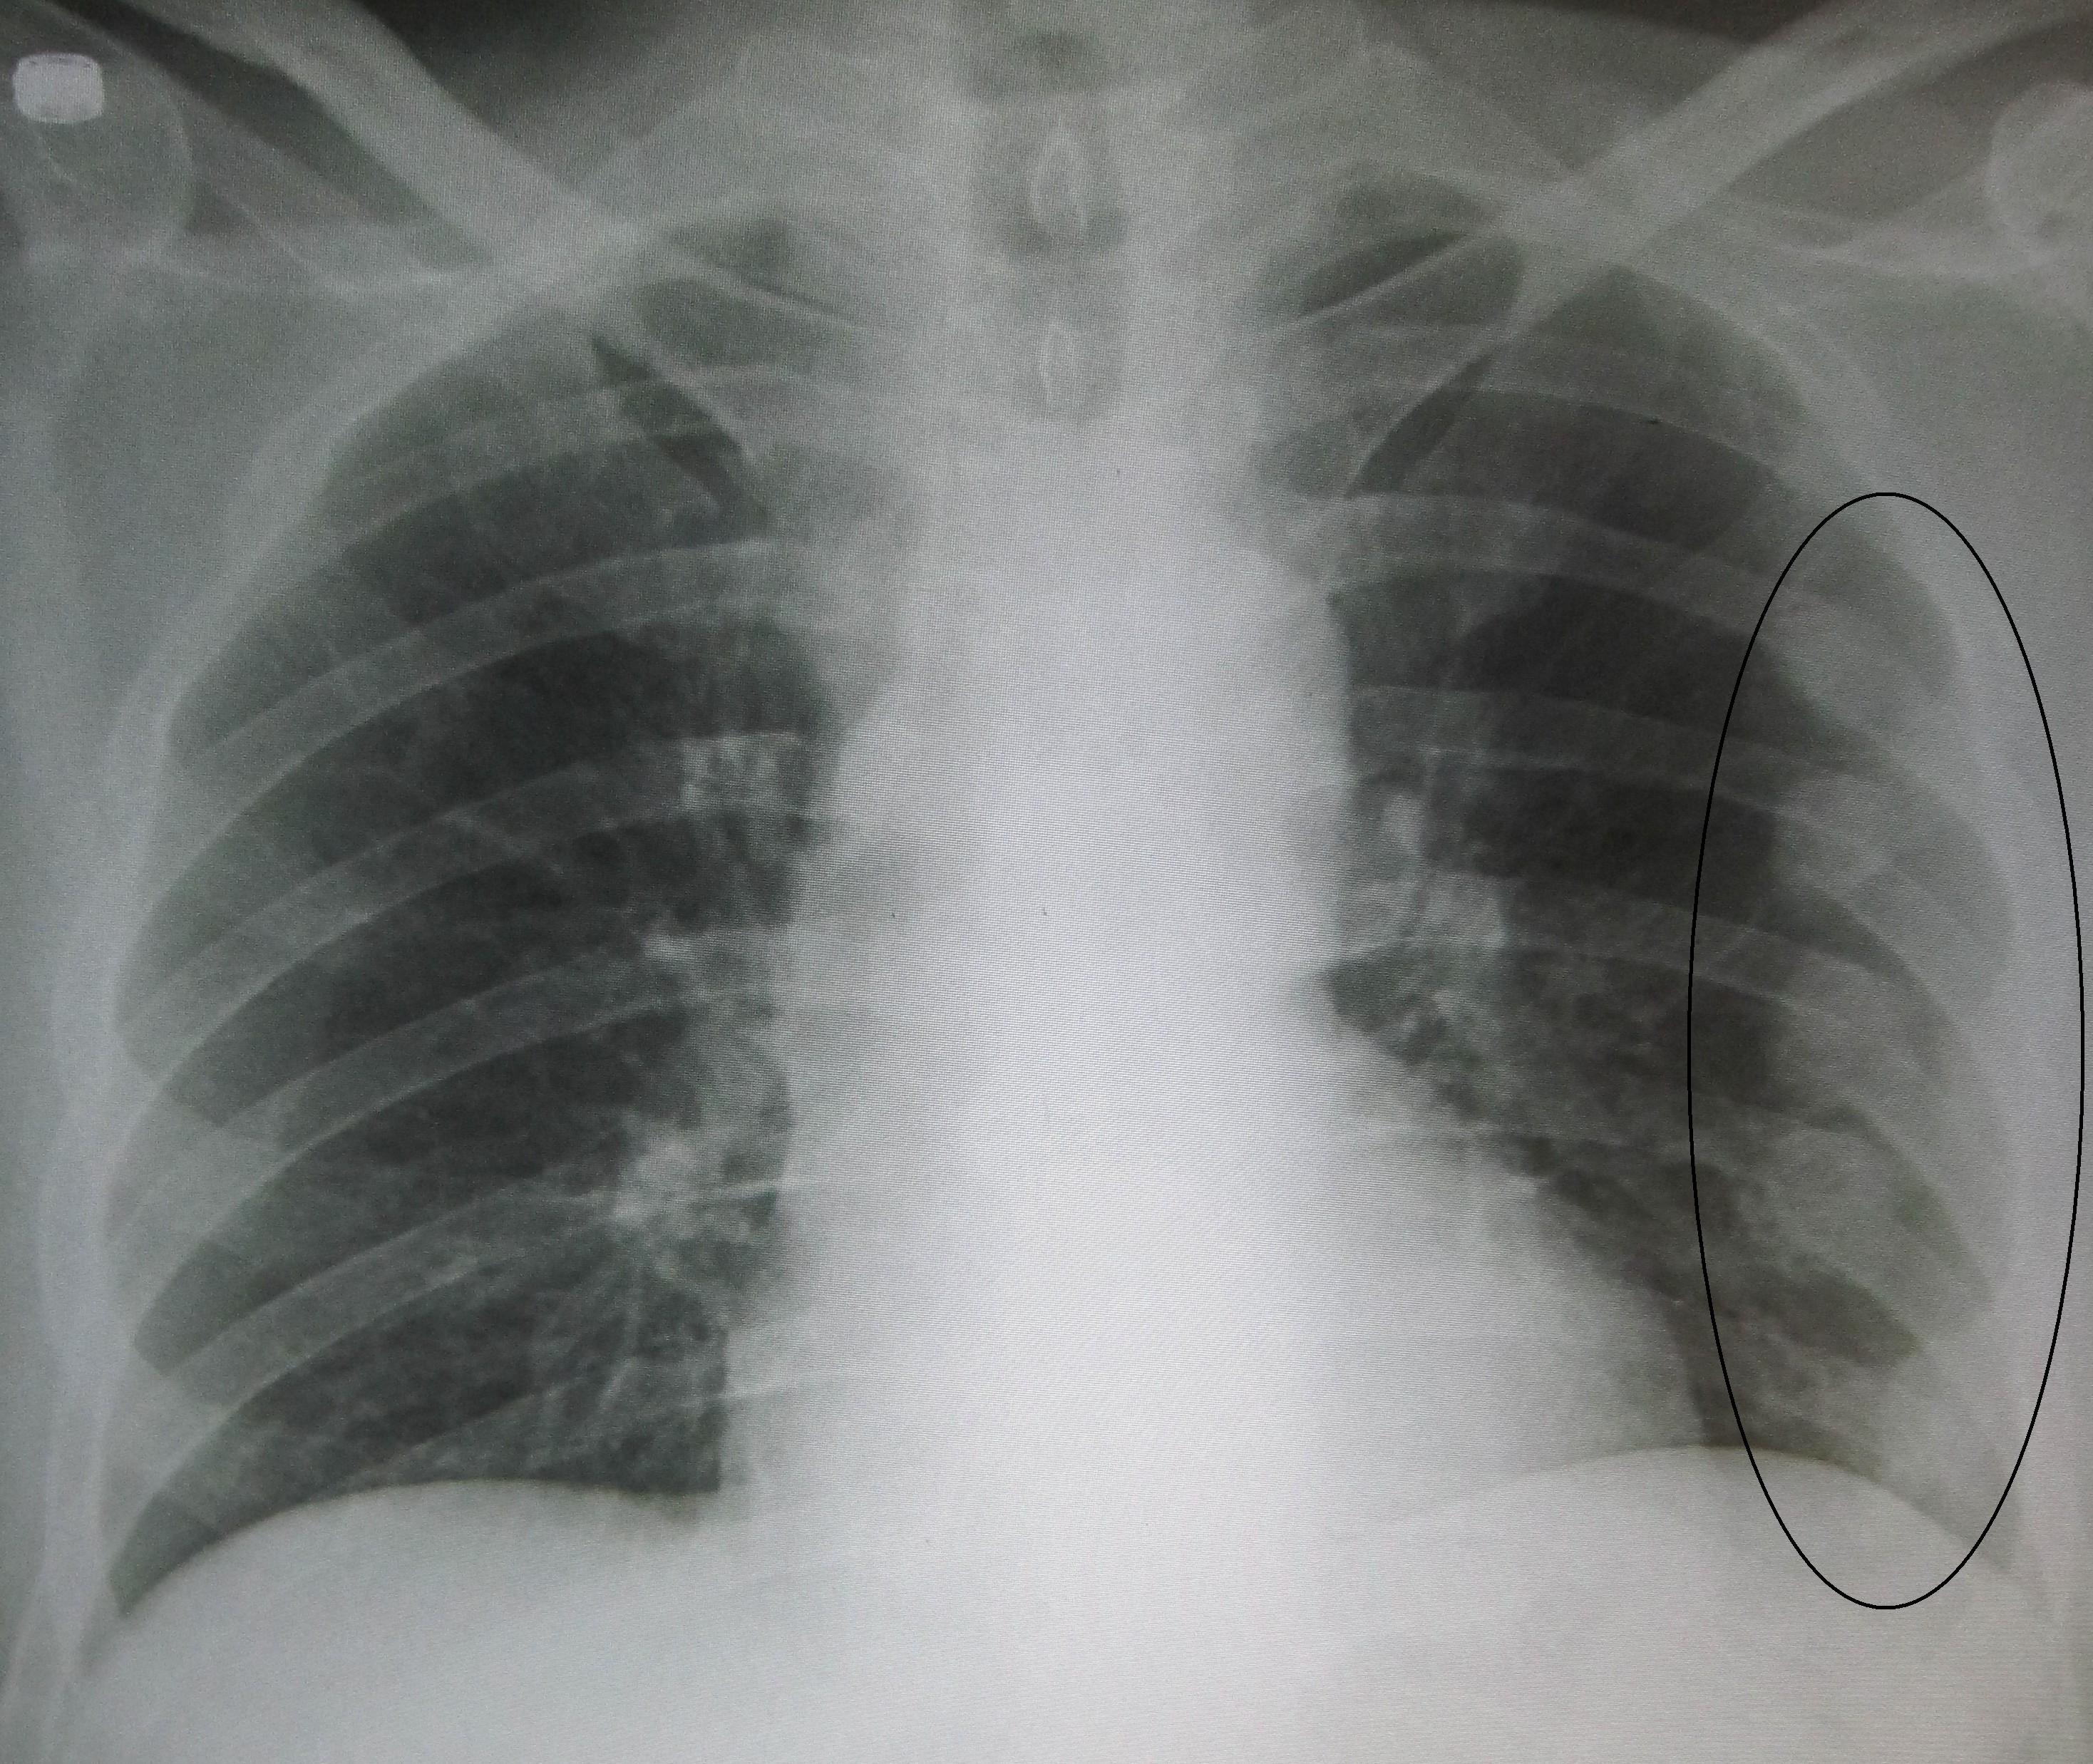

Rib Fracture Ct Scan Spirometer For Broken Ribs  Evidence on the effectiveness of incentive. Spirometry measurements (ie, incentive spirometry volume, forced vital capacity, forced expiratory volume in one second, and. Our results suggest that unsupervised incentive spirometry does not prevent delayed atelectasis, pneumonia, or. Your doctor may recommend an incentive spirometer before or after surgery, or if you have a broken rib, pneumonia, or chronic. Pulmonary complications (pcs). Spirometer For Broken Ribs.